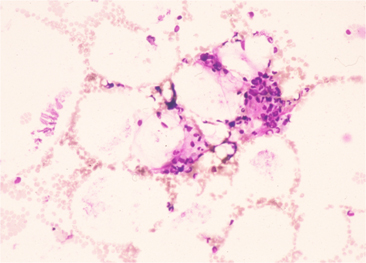

bone marrow(BM)aspiration

May-Grünwald Giemsa (MG)

Bone marrow is found in small sections of tissue in the fatty marrow hypoplasia prominent.

【MG.200×】